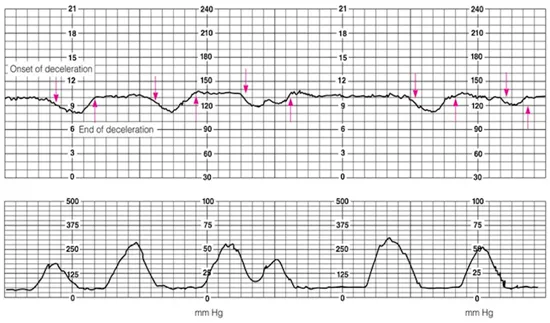

• Fetal CTG상 FHR 감소가 uterine contraction과 무관하게 나타나며, decline의 onset부터 nadir(최저점)까지 30초 이하이므로(별다른 표기가 없을 경우 작은 한 칸이 10초) variable deceleration으로 진단한다.

39주차 초산모가 유도 분만을 위해 옥시토신을 투여받고 있다. 혈압은 128/78mmHg, 맥박은 85회/분, 호흡은 18회/분, 체온은 36.5℃로 측정되었다. 자궁경부는 4cm 개대, 70% 소실, 하강도 -1을 보이고 있으며, 전자태아심음감시장치를 통해 모니터링 중이다. 태아는 두위로, 예측태아몸무게는 3050g(50백분위수 3070g)으로 추정된다. 태반 상태는 정상적이다. 필요한 처치는 무엇인가?

Recurrent variable deceleration이 있으므로 자궁수축제를 중단한다.

체위 변경 (lateral decubitus), 산모 산소 투여, 수액 공급, 자궁수축제 중단 등 태반 혈류를 증가시키는 조치를 취하며 이후 처치에도 호전 없을 경우 제왕절개를 고려한다.